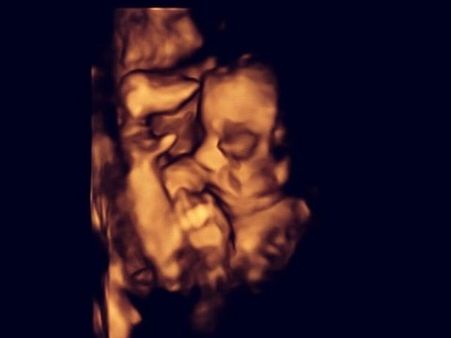

The 26-year-old woman and her partner were given the option to terminate the pregnancy after the tests revealed that the unborn baby had spina bifida. The medics discovered this in a routine 20-week scan where they realised that the unborn baby's head was not the right measurement.

The doctors offered the couple a new option called as foetal surgery where they would fix the unborn child's condition even before she is born. The surgery involved removing the unborn baby from the mother's womb and repairing the spinal cord of the child, so that the baby has greater chances of leading a normal life.

The Baby Was Later Put Back In The Womb

Doctors revealed that the baby was then later placed back in the mother's womb to complete the pregnancy term. The medics also revealed that the surgery was a success and revealed that people can opt for this surgery as studies revealed that about 80% of babies are terminated after their parents know about the baby's condition.